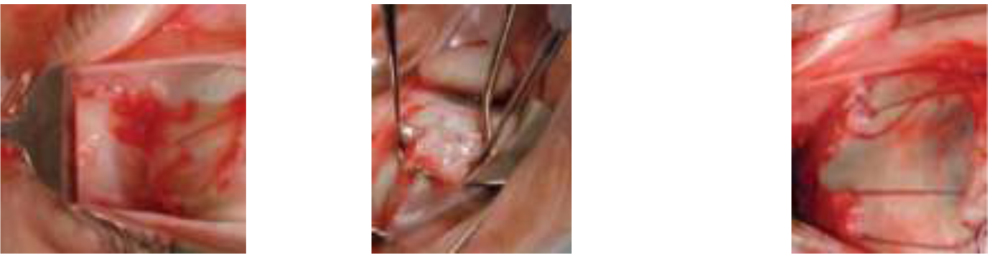

Figure: 2. Lateral rectus resection and Y-split LR exposure. LR split with hook. LR resection with splitting